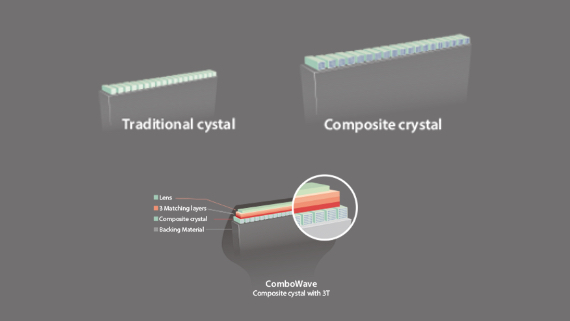

Fortgeschrittener Echo-Boost

Mindrays konsekutiver Durchbruch hin zu allerbester Ultraschall-Bildgebung.